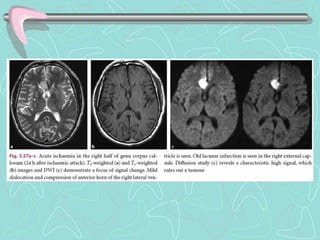

RESONANCIA MAGNETICA

•Útil en Ictus Isquémico Agudo, menor de 6h, con mejor sensibilidad

que TC

•RMN secuencia de Difusión y Perfusión, para menores de 3 horas

•No útil en Ictus hemorrágico agudo